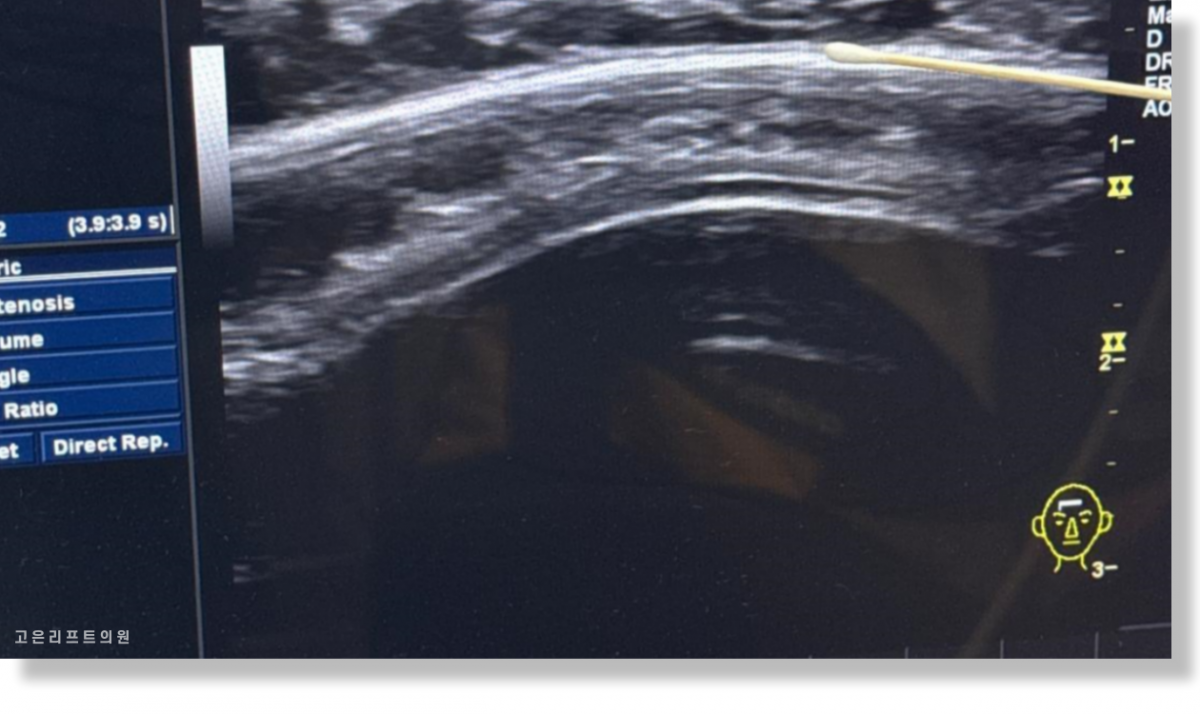

3. 초음파 진단이 중요한 이유

부산 이마필러녹이기 과정에서

가장 중요한 첫 단계는 정확한 진단입니다.

초음파 검사를 통해

필러의 정확한 위치

피부층인지, 근육층인지

남아 있는 양과 분포 상태

를 확인한 뒤에야

어떤 방식으로 제거하는 것이 안전한지 결정할 수 있습니다.

초음파 검사 시 필러가 캡슐화된 이물질처럼 확인됨